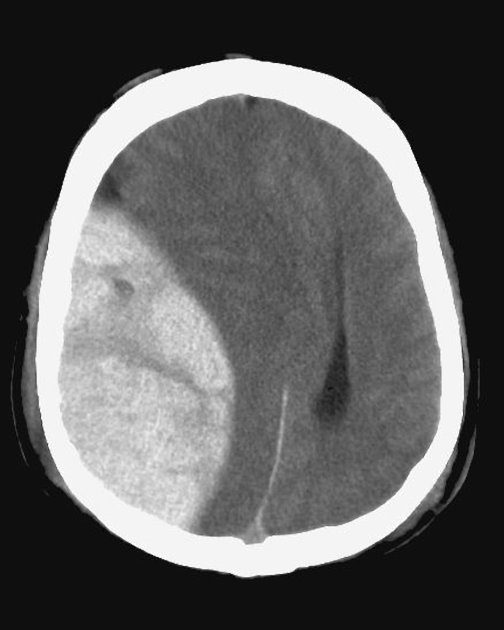

L'emorragia intraventricolare è un sanguinamento all'interno dei ventricoli cerebrali.

La presenza di emorragie intraventricolari può essere indagata tramite angio-TC, risonanza magnetica e angiografia cerebrale.